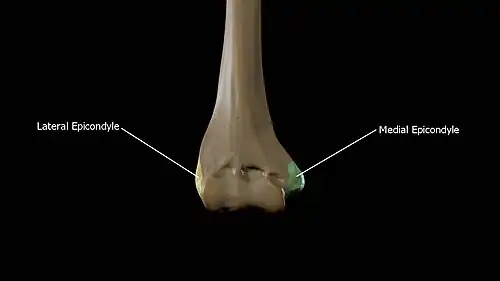

The distal or lower extremity of the humerus is flattened from before backward, and curved slightly forward; it ends below in a broad, articular surface, which is divided into two parts by a slight ridge. Projecting on either side are the lateral and medial epicondyles.

Epicondyles

- The lateral epicondyle is a small, tuberculated eminence, curved a little forward, and giving attachment to the radial collateral ligament of the elbow-joint, and to a tendon common to the origin of the supinator and some of the extensor muscles.

- The medial epicondyle, larger and more prominent than the lateral, is directed a little backward; it gives attachment to the ulnar collateral ligament of the elbow-joint, to the pronator teres, and to a common tendon of origin of some of the flexor muscles of the forearm; the ulnar nerve runs in a groove on the back of this epicondyle.

The medial supracondylar crest forms the sharp medial border of the distal humerus continuing superiorly from the medial epicondyle. The lateral supracondylar crest forms the sharp lateral border of the distal humerus continuing superiorly from the lateral epicondyle.[3]